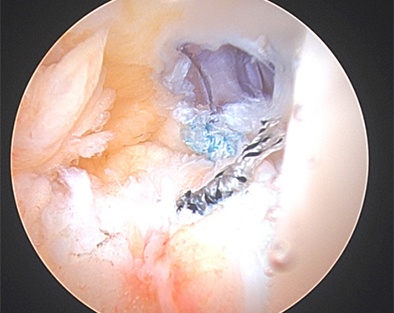

Figure 4

As such, during a diagnostic arthroscopy at the very beginning of an ACL reconstruction, is important to look closely in the back of the knee near the attachment of the posterior horn of the medial meniscus to see if there is a disruption in the capsule. If there is a tear in this capsule region, it is debatable on which ramp tears are considered stable versus unstable. Nonetheless, it is important to discuss your surgeon's approach to ramp lesions and threshold to repair them. In our practice, we repair nearly all ramp lesions identified during the diagnostic arthroscopy. In fact, Dr. Momaya’s team has published a novel anchor based technique for ramp repair. Figure 2-4 demonstrates the repaired ramp lesion in a collegiate football athlete via a lasso and suture technique.